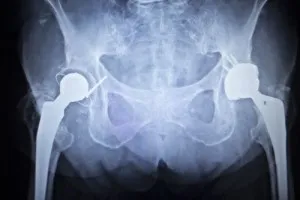

A metal-on-metal hip implant is a special class of artificial hip joint. When the cartilage and bone of the hip wears down from age, disease, or injury, surgeons can replace the joint with an implant, attaching to the top of the femur (upper leg bone) and the socket of the pelvis.